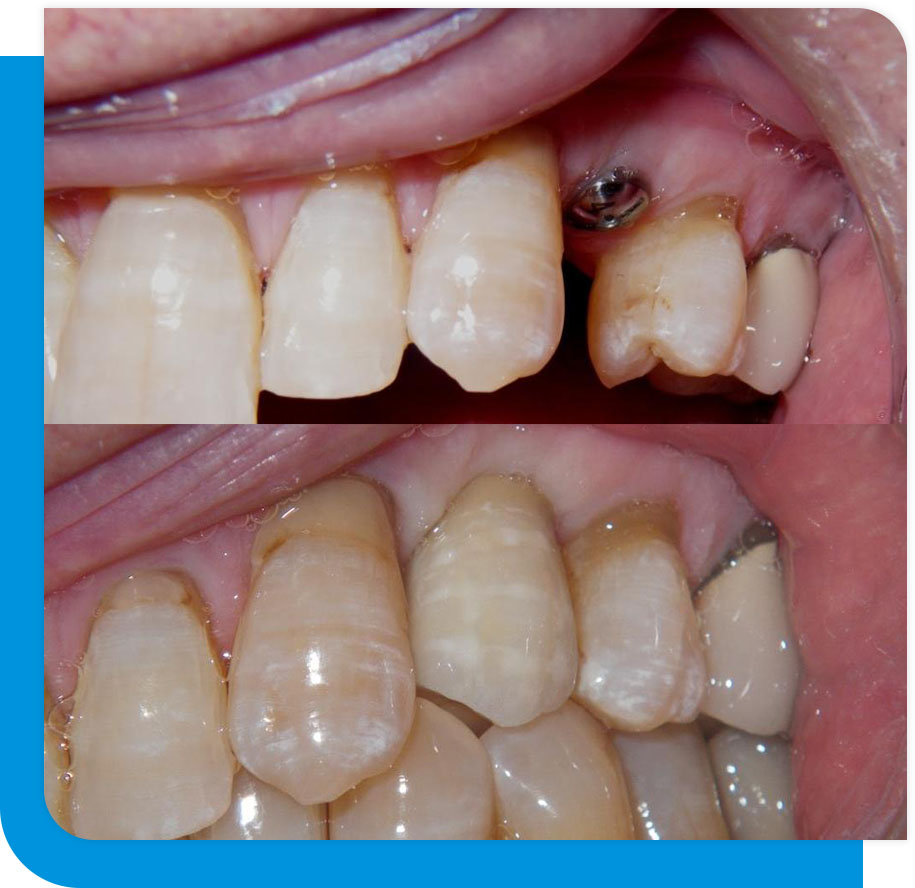

You can have temporary crowns fitted so you can eat and speak normally during this healing period and keep a pleasing look for your smile.

It’s time to attach an abutment to the implant after it has healed. Your new tooth’s abutment acts as its foundation. In order to produce your permanent repair, an impression of the abutment is obtained after it has been positioned. The crown will then be made using this in our lab.

You can come back to the office to permanently affix the restoration once the work is finished. After a few period of getting acclimated to the implant, your smile will appear just like it did before, and it will feel exactly like one of your natural teeth.

The next best alternative to your teeth is provided by dental implants. They mimic your real teeth in appearance and feel. They make your mouth and grin look better. You are not limited to a specific diet when you have dental implants; you can chew gum and eat corn on the cob. Additionally, dental implants lessen the bone atrophy and shrinking that come with missing teeth.